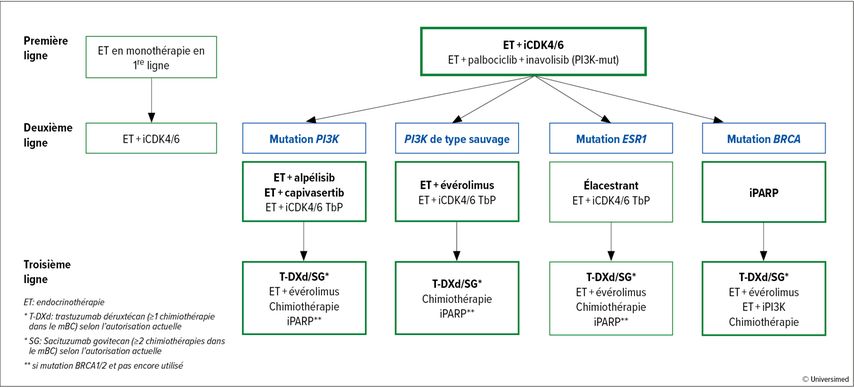

Un algorithme actuel pour le traitement du cancer du sein HR+/HER2– avec une récidive pendant ou après l’ET adjuvante prévoit pour la majorité des patient·es un traitement de première ligne par ET et inhibition de CDK4/6 (Fig.1). Ensuite, une approche individualisée est envisageable en fonction de la configuration génétique, et le T-DXd ainsi que le SG sont disponibles dans les autres lignes de traitement. Il faut également toujours penser à une mutation BRCA1 ou 2 comme cible supplémentaire, car des thérapies ciblées par inhibiteurs de PARP sont disponibles dans ces cas.

Fig.1: Algorithme thérapeutique dans le cancer du sein à récepteurs œstrogéniques positifs/HER2 négatif avec récidive après ou pendant l’endocrinothérapie adjuvante (les traitements de prédilection sont mis en évidence en gras, les autres sont d’autres options possibles)